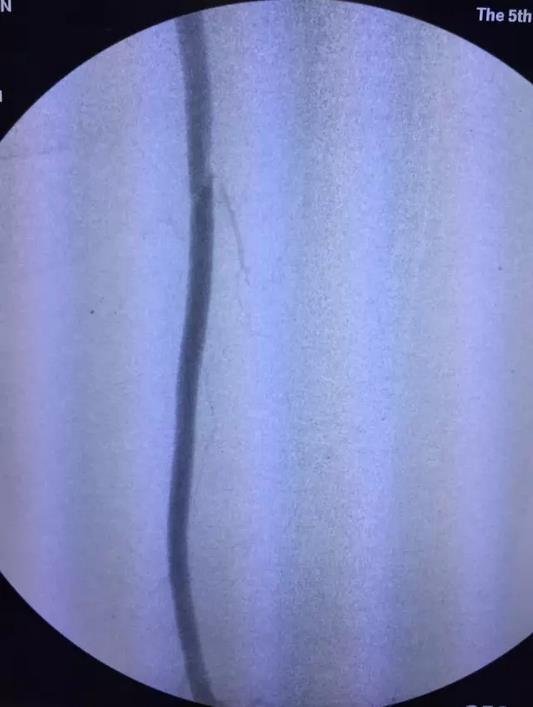

术后因患者长时间留置动脉鞘管,易导致菌血症、鞘管内血栓形成等并发症。施敏护士长带领的护理团队术后严格无菌操作,按时冲洗鞘管,避免了上述并发症的发生。5天后复查造影(图3,4,5,6,7):腹主动脉,左侧髂动脉,股动脉全程通常,膕动脉短段闭塞,但周围侧枝血管丰富,可较好的代偿至膝下。患者左下肢的皮肤温度和颜色明显改善,下肢疼痛,发凉等缺血症状缓解,出院前复查CTA效果良好(图8)。

图5 溶栓后股浅动脉造影

图6 溶栓后膕动脉造影